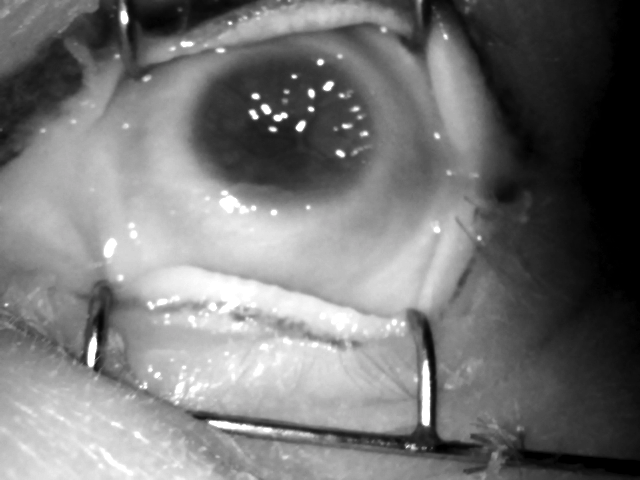

(d) Post-mortem Samples

Figure 1: Illustration of live iris images, compliant with ISO/IEC 19794-6 (a), and presentation attack instruments popular in research databases (b-e). The top (d) image is an early-stage post-mortem sample whereas the bottom sample shown in (d) represents a later-stage capture. The example shown in top (e) picture illustrates the generation of synthetic iris texture by combining bona fide iris texture patches to form a new iris texture. The examples shown in bottom (e) section illustrate synthetic irises generated by a Generative Adversarial Network (GAN) developed by [42]. Note that some departures from a live iris are easy to observe, such as an extra pattern overlaid on the actual iris tissue (printouts and textured contact lenses) or metal retractors (post-mortem cases). It may be, however, harder to judge on the authenticity of an iris image in case of good-quality synthetic samples and newly deceased post-mortem samples.

As shown in [33], the irises of deceased individuals can also be used as a presentation attack instrument. For some number of hours post-mortem, the texture of the iris remains intact enough to deceive an iris PAD system. Hypothetically, the post-mortem iris could be used as an impostor attack of the deceased individual. However, more realistic is that someone may use an image of a post-mortem sample to hide their identity. Post-mortem iris samples closely resemble live irises in the early stages after death. Thus, detecting these samples in the wild may prove difficult.